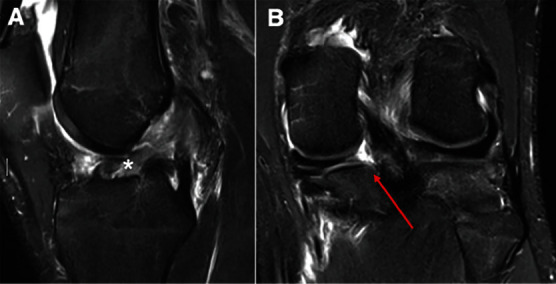

在急性前十字韧带(ACL)断裂的情况下,合并内侧和外侧后半月板根撕裂的情况极为罕见。以下病例报告显示,一名高中橄榄球运动员在训练中做旋转动作时膝盖非接触性受伤。患者是一名 17 岁的高中橄榄球防守后卫,受伤一周后到诊所就诊,主诉膝关节持续疼痛,伴有肿胀,活动范围(ROM)受限,并主诉膝关节不稳定。体格检查时发现患者膝关节前十字韧带松弛。磁共振成像(MRI)显示前交叉韧带中段完全撕裂,内侧半月板后角信号增强,外侧半月板局部无明显病变迹象。患者接受了前交叉韧带重建术(ACLR),术中发现内侧和外侧根部均有撕裂。手术采用标准的髌腱骨(BTB)自体移植前交叉韧带重建术,利用经胫骨牵引法对内侧和外侧根部进行联合修复。其临床意义在于,半月板根部撕裂伴有前交叉韧带撕裂很难在术前核磁共振成像中诊断出来,尤其是在侧方,因此在关节镜检查时仔细评估两个半月板根部至关重要。此外,为避免与前交叉韧带胫骨隧道合并,仔细创建经胫骨修复所需的半月板根修复隧道至关重要。

Combined medial and lateral posterior meniscal root tears in the setting of an acute anterior cruciate ligament (ACL) rupture are extremely rare. The following case report demonstrates a high school football player who sustained a noncontact knee injury while performing a spin move at practice. The patient is a 17-year-old high school football defensive end who was presented to the clinic 1 week following the injury complaining of persistent knee pain with associated swelling, limited range of motion (ROM), and complaint of instability. During physical examination, the patient was found to have anterior cruciate laxity. Magnetic resonance imaging (MRI) demonstrated a complete midsubstance tear of the ACL and increased signal within the posterior horn of the medial meniscus with no obvious signs of pathology localized to the lateral meniscus. ACL reconstruction (ACLR) was performed and intraoperatively, both medial and lateral root tears were found. A standard bone patellar-tendon bone (BTB) autograft ACLR was performed with combined medial and lateral root repair utilizing a transtibial pull-out method for both. The clinical importance is root tears with associated ACL tears can be hard to diagnose on preoperative MRI, especially laterally, so careful assessment of both meniscal roots at the time of arthroscopy is critical. Furthermore, careful creation of the needed root repair tunnels for transtibial repair is critical to avoid coalescence with the ACL tibial tunnel.